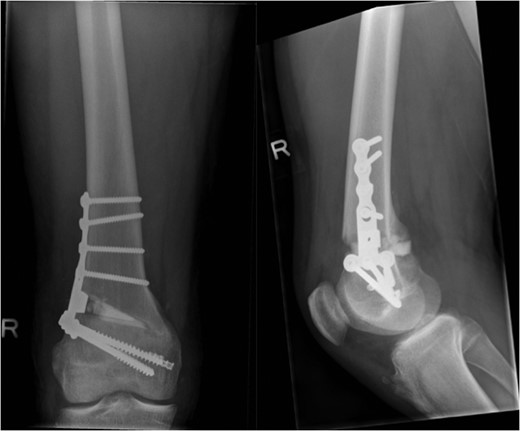

The patient was counseled as to the nature of their injury and the likelihood of ongoing instability and potential for early degenerative change with conservative management. The deformity and instability were successfully treated with an opening distal femoral osteotomy combined with surgical plication of the MCL (Figs 6 and 7). At the time of reporting, 2 years following surgery, the patient has successfully returned to playing competitive football without symptoms of instability. The metalwork remains in situ.